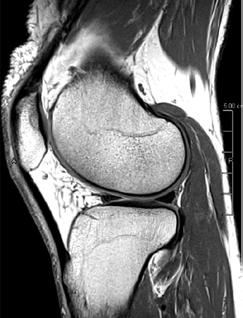

PD STIR - 1024 x 1024 matrix - 3mm slice thickness

Sag T2 - 0.5 x 0.5 min - 0:56 min Ax PD FatSat - 0.6 x 0.6 mm - 1:30 min Cor PD FatSat - 0.6 x 0.6 mm - 1:15 min Cor PD - 0.5 x 0.5 mm - 0:58 min © 2020 CANON MEDICAL SYSTEMS // MREU200040

Fast knee protocol with AiCE on Vantage Orian 1.5T